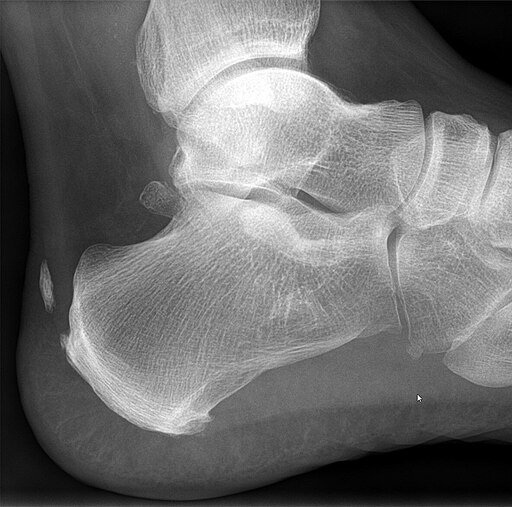

- مشاكل بنيوية: مثل القدم المسطحة (Flat feet)، أو وجود نتوء عظمي في مؤخرة الكعب (Haglund’s deformity) الذي يسبب احتكاكاً ميكانيكياً بالوتر.

- نتوءات عظمية (Bone Spurs): قد يحاول الجسم “إصلاح” الالتهاب المزمن عن طريق تكوين ترسبات عظمية صغيرة عند نقطة اتصال الوتر بالكعب، مما يزيد الألم والاحتكاك.